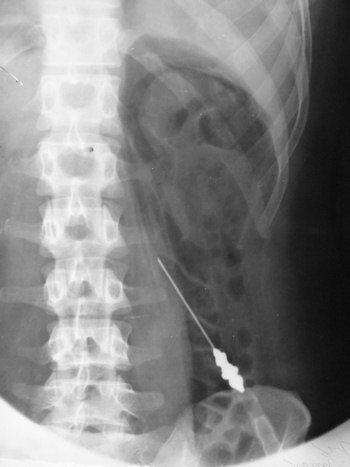

Retroperitoneal air studies

In this technique, the retroperitoneum around the kidney is outlined by gas. Paul Rosenstein from Berlin and Humberto Carelli from Buenos Aires described the technique independently in 1921. A 10-cm needle was used to make a retroperitoneal injection. Rosenstein injected 600 mL of oxygen and Carelli about 200-400 mL of carbon dioxide. The examination was introduced in the days before the IVU to show the kidney. Rosenstein emphasized that it was "important that the radiologist became independent of the clinician for these pictures." He thought this technique was of value in the following:

Determining the presence of one or both kidneys. Removal of a solitary kidney would be a disaster.

Determining the size of a kidney.

Showing the presence of kidney stones more clearly.

Looking for displacements of kidneys. This would diagnose the "floating kidney" that was thought to be a cause of symptoms as a part of visceroptosis.

Diagnosis of renal tumors and tumors around the kidney.

Studying "acute stresses" of the kidney. In unexplained renal colic, the enlarged pelvis could be shown outlined by gas.

In later years, the technique was combined with tomography to show the adrenal gland. The examination illustrated below was performed in 1943.